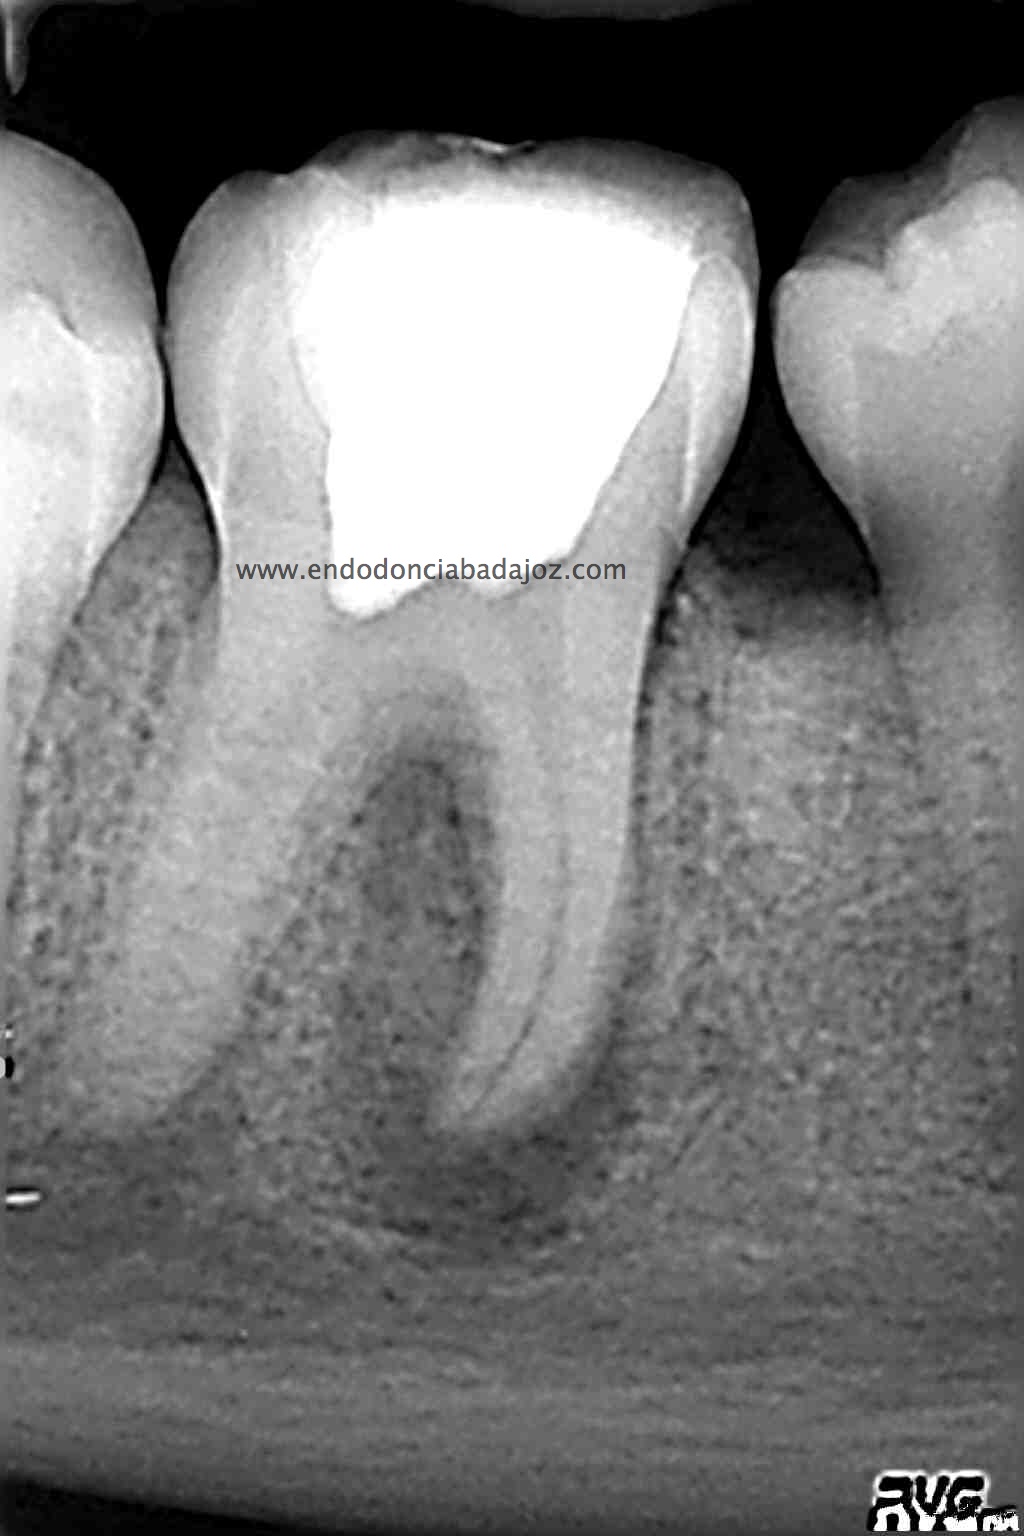

Una vez que hemos limpiado los conductos con un sistema de instrumentación  Protaper en combinación con limas K3. Pasamos a obturar los mismos con una técnica de condensación vertical de ola contínua de Buchanan y un backfilling con la gutapercha inyectada de la pistola ObturaII. Tomamos varias proyecciones, orto-mesio-distal

Con estas tres proyecciones nos quedamos mucho más tranquilos y seguros de un buen sellado hermético y tridimensional des sistema de conductos de esta pieza.

Llamamos a revisión 9 meses después a nuestro paciente: